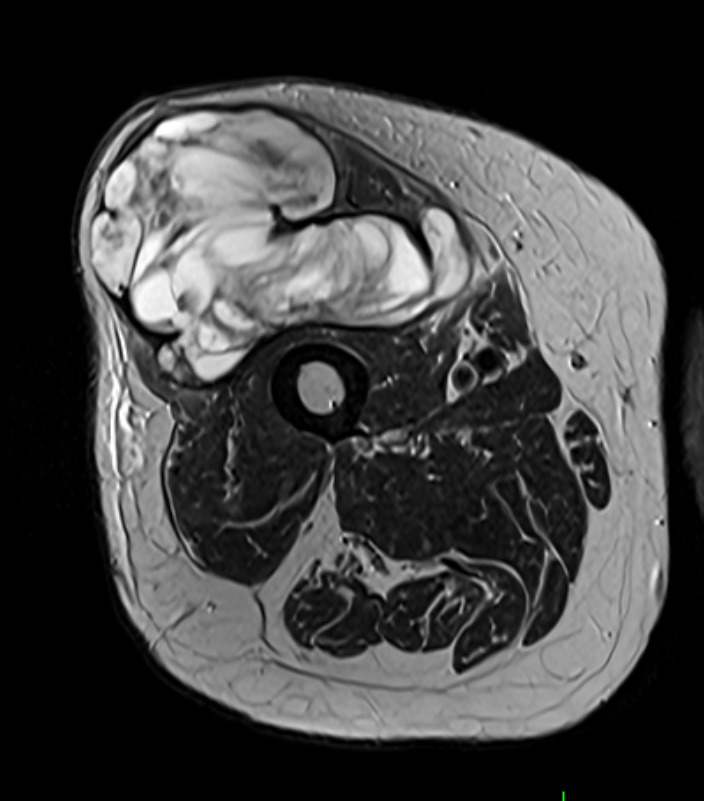

Muscle Cancer